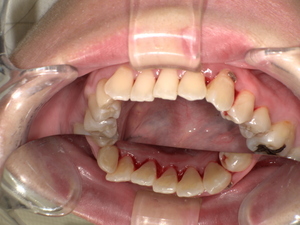

【ビフォーアフター】クリーニングの効果

施術後は:

- 歯がツルツルになる

- 口の中がスッキリする

- 口臭が軽減する

- 自然な白さになる

👉 1回でも変化を実感する方が多いです